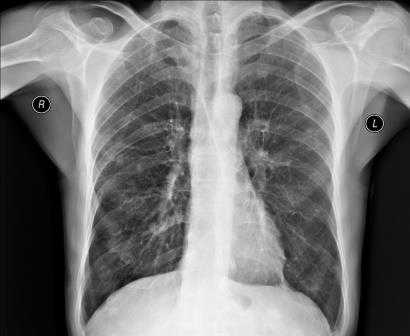

Рентгенография грудной клетки - это метод диагностики, позволяющий получить изображение органов грудной полости с помощью облучения рентгеновыми лучами. Различные ткани организма в зависимости от своей плотности по-разному пропускают рентгеновы лучи, а значит, по-разному отображаются на снимке (рентгенограмме).

Рентген грудной клетки дает возможность изучить костные структуры (ребра, грудину, позвоночник), легкие, плевру, бронхи и трахею, сердце и средостение, а также оценить состояние мягких тканей этой области.

Рентген грудной клетки